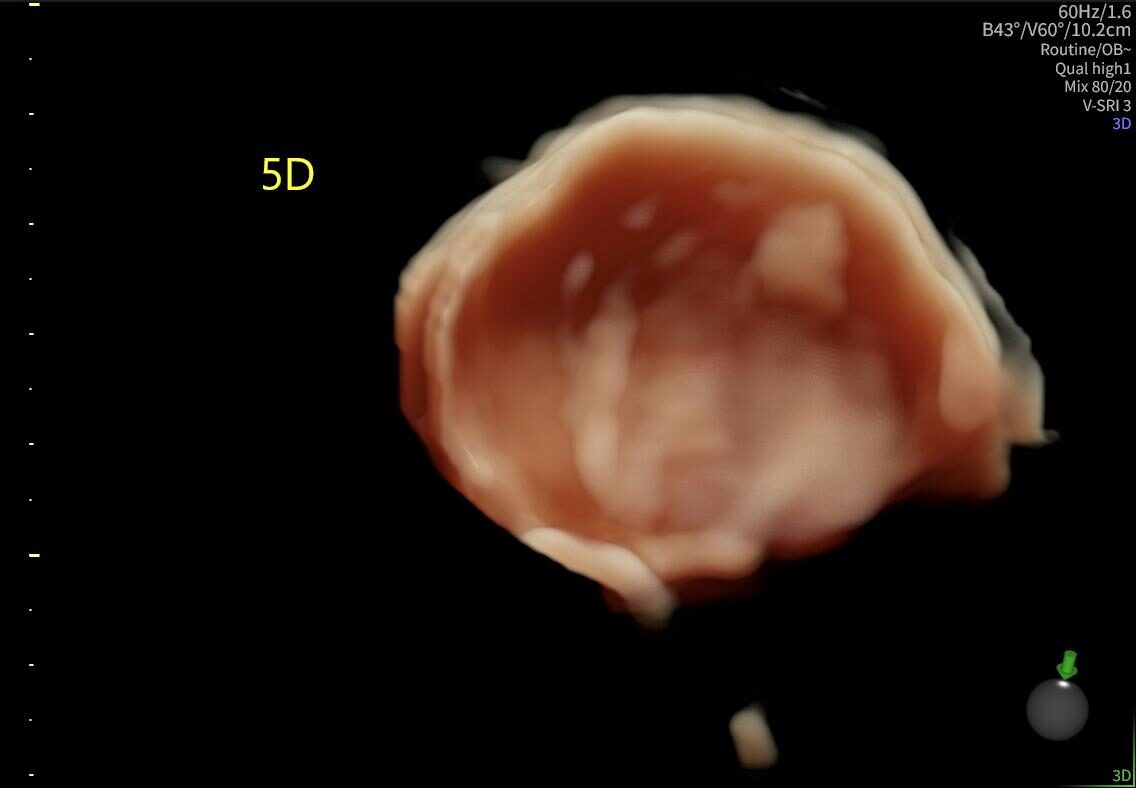

La ecografía ginecológica es un estudio por imágenes no invasivo que permite evaluar de forma precisa el útero, los ovarios y el sistema reproductor femenino. Es una herramienta fundamental para la detección temprana de alteraciones ginecológicas, el seguimiento de tratamientos y los controles preventivos.

En OBGYN Perú, realizamos ecografías ginecológicas con equipos de alta resolución, garantizando resultados confiables y una atención médica especializada.